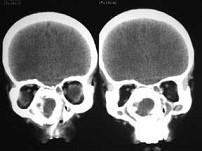

问题 女,14岁,渐进性鼻塞2年余,右眼肿痛数月,CT如图所示,应诊断为 ( )

选项 A、筛骨结核 B、筛骨骨化性纤维瘤 C、筛骨骨纤维瘤 D、筛骨软骨瘤 E、筛骨骨肉瘤

答案 B